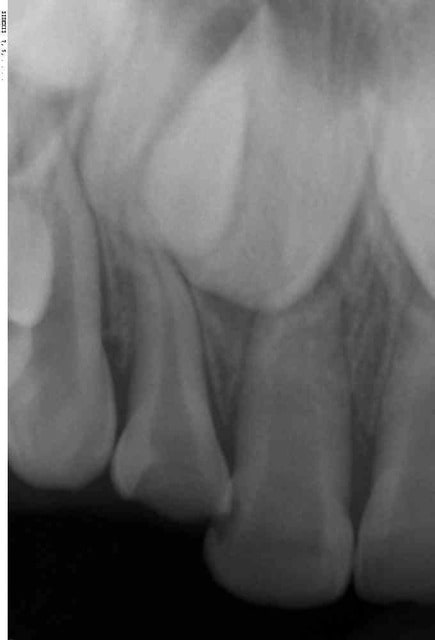

j'ai reçu une petite de 4 ans d'origine asiatique ( pigmentation). Elle est tombée il y a 15j, ses parents l'ont amenée aux urgences pédiatriques à l’hôpital car elle avait un gros œdème a la lèvre

aujourd’hui présence d'un liserer rouge au collet de 51 et 52 et au niveau des apex de ces mêmes dents il y a une tuméfaction dure. Pas de douleur, elle mange normalement

mouvement de la 11, c'est effectivement ce que j'ai craint surtout vu son inclinaison. C'est pour cela que j'ai fait (et vous ai mis) une radio de 21 mais même inclinaison

nécrosée elle doit l'être vu sa couleur

pas de mobilité de 51 par contre c'est la perte d'attache au collet qui me stress